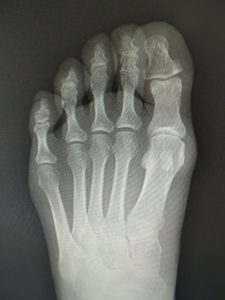

手術前 手術後4年

手術前 手術後

真田理事長による手術の様子。外反母趾|症例 (左から 手術前、手術後、ワイヤ抜去後)